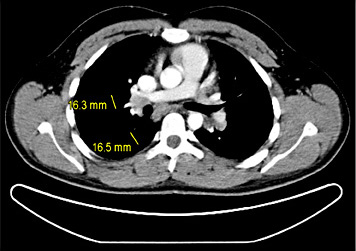

5th patient: this 23-year-old man underwent orchiectomy for marker-negative testicular seminoma at another institution. CT revealed intrathoracic nodules suspicious for mediastinal lymph node metastases. Accordingly, 4 cycles of BEP chemotherapy were administered. Restaging revealed unchanged mediastinal lymphadenopathy (Fig. 4). Then, the patient was referred to our institution for further management. Thorough pulmonological examination including transbronchial biopsy disclosed sarcoidosis-like lymphadenopathy, and thus metastatic disease was excluded. In view of these results, it must retrospectively be assumed that this patient had sarcoidosis synchronously with seminoma rather than having metastatic disease. Accordingly, the serum miR371a-3p level was RQ = 0.0 at the time of re-staging after chemotherapy. Unfortunately, no miR-levels were measured at the time of first presentation. Although speculative, one would assume that miR371a-3p levels had probably been low after orchiectomy for seminoma because the mediastinal lymphadenopathy had not changed ever since. By retrospective consideration, the normal marker level would have indicated the absence of metastases at the outset and accordingly, the patient could have been spared unwarranted chemotherapy and excessive diagnostic procedures apart from emotional distress from extended treatment.

Chest CT of patient #5 after 4 cycles of cisplatin-based chemotherapy: hilar lymphadenopathy. Transbronchial biopsy revealed sarcoidosis.

Conversely, serum levels of miR371a-3p can also help to exclude metastatic GCT as documented in case #5, where the normal level of miR371a-p could have helped to correctly assess ambiguous radiological findings and thus exclude metastatic disease.